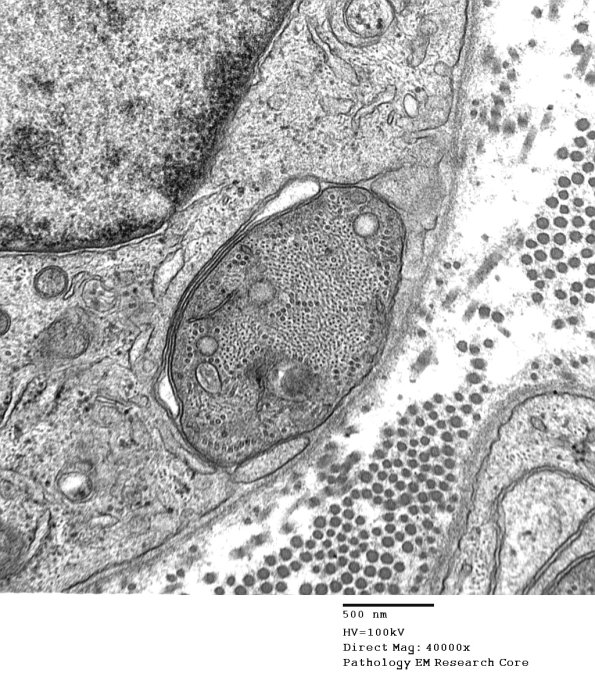

A small apparently previously myelinated axon shows similar prominent cytoskeleton and surrounding reactive Schwann cell cytoplasm. (electron micrograph)